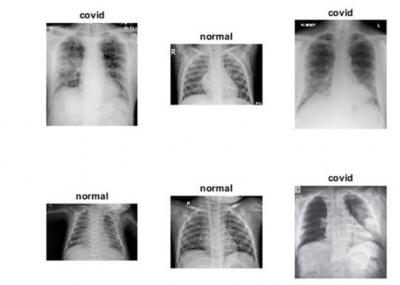

सॉफ्टवेअर कोड व्यक्तीची छाती स्कॅन करून शरीरात लपून बसलेल्या कोरोनाचा शोध घेऊ शकतं असा दावा नारायणन यांनी केला आहे.

कोरोनासाठी तयार करण्यात आलेले हे खास सॉफ्टवेअर सामान्य एक्स रे स्कॅनिंग मशीनपेक्षा एकदम वेगळं आहे. आर्टिफिशिल इंटेलिजन्सच्या मदतीनेच तयार करण्यात आले आहे.